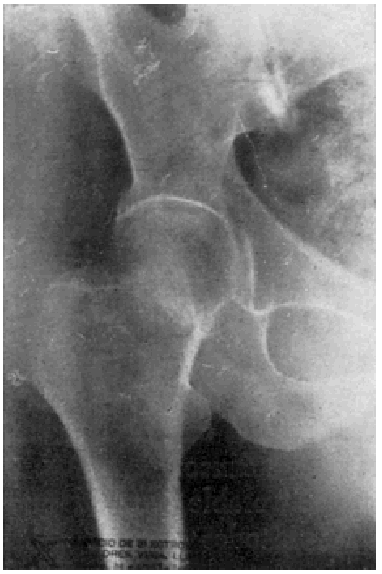

Fracaso número 4(observación número 21). Josefa T., setenta años. Afecta de síntomas de reblandecimiento cerebral. Dos meses antes de producirse la fractura, en un intervalo de quince días, tuvimos que extraerle por dos veces una cánula de lavativa de su ampolla rectal. La fractura fue tratada con el clavo de Sven Johansson (fig. 6. A y B), según la técnica habitual. A los veinte días de la intervención tuvo que pasar a su domicilio ante las quejas de los enfermos de las habitaciones próximas. La enferma estaba en una agitación constante y se quejaba continuamente. En su domicilio, donde la vigilancia no era tan severa como la de la clínica, abandonaba el lecho con frecuencia. Al mes y medio de la intervención notaron los familiares que la enferma, a pesar de su agitación, permanecía siempre en el lecho. Explorada entonces por nosotros, después de haber transcurrido una semana sin haberla visitado, comprobamos que el clavo hacía una prominencia bajo la piel, que estaba a punto de ser perforada.

Figura 6. A: obs. núm. 21. Radiografía practicada antes de la penetración completa del clavo, que en esta proyección está situado algo cranealmente. B: obs. núm. 21. Radiografía practicada antes de la penetración completa del clavo. La situación de éste es buena; con relación a la cabeza, es ligeramente ventral, debido a que la fractura no ha sido perfectamente reducida.

A pesar de que la situación del clavo no era ideal en este caso, no hay duda de que el resultado desfavorable obtenido fue condicionado por el estado mental de la enferma, la cual, o no hubiera tenido que ser operada, o, en todo caso, sometida, en el curso postoperatorio a una vigilancia más estricta.